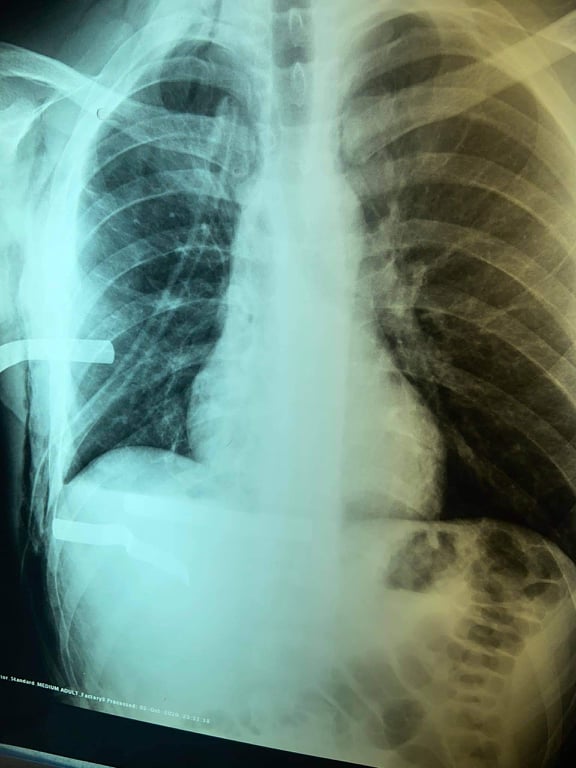

وقال أخصائي جراحة القلب والصدر والأوعية الدموية ، الدكتور حسنين العكلة الموسوي ، في بيان صحفي تلقت ( وكالة نون الخبرية ) نسخة منه ، إنه " نجح وبمًساعدة أخصائي التخدير ، الدكتور كفاح عودة ، والمُقيم الأقدم ، رُسل عبد الرضا ، في إنقاذ حياة أحد زائري الأربعين من خدمة المواكب الحُسينية بعد سقوطه على سيخ معدني ( شيش ) ، وأصاب قلبه إصابة بليغة " ، مُبيناً أن " المصاب كان فاقداَ للوعي لحظة وصوله إلى صالة الطوارئ ، وبحالة صدمة وعائية حادة ، بسبب النزف وكانت حالته حرجة جداً ، غير إن تدخل العناية الإلهية والخبرة الجيدة التي يتمتع بها الملاك الطبي في التعامل مع الحالات المرضية الطارئة والحرجة " ، فضلاً عن " توفر الأجهزة الطبية التخصصية الحديثة ومن مناشئ عالمية رصينة ومتطورة ، جعل الأمور تسير بشكل طبيعي ".

وتابع ، أن "العملية إستمرت نحو ساعتين ، وتُعد من العمليات النادرة جدا التي يتم فيها إنقاذ المصاب في القلب ، حيث تمكنّا خلالها من فتح الصدر ، وإصلاح عضلة القلب المتضررة الى جانب السيطرة على النزف فيها"، مؤكداً أن "المصاب إستعاد وعيه ، بعد تماثله للشفاء تدريجياً ، وإستقرار وضعه الصحي ، وغادر المدينة الطبية بعد رقوده فيها لمدة أربعة أيام وهو بصحة جيدة ". ولفت الموسوي ، إن " الملاك التمريضي المُشارك في العملية ، كان مؤلفاَ من (وسام صالح مهدي، ونجم عبد الزهره عبد علي ، وضرغام صبيح حمادي ، وحوراء رضا يحيى ، وكرار علي كاظم)